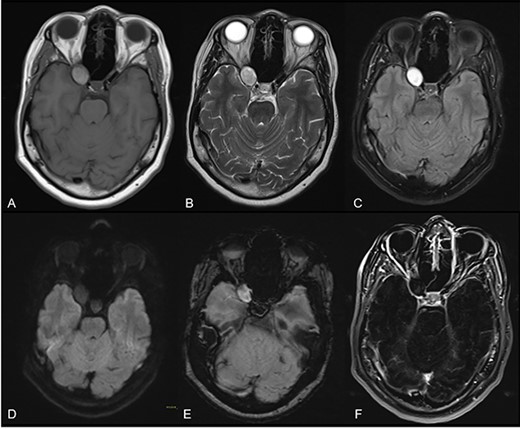

At arrival, under the suspicion of a supraclinoid internal carotid aneurysm, an MRI angiography was performed, evidencing a rounded proteinaceous mass in the right ACP with compression of the optic nerve suggestive of an ACP mucocele (Fig. 1). No vascular abnormalities were demonstrated. A conventional subtraction angiography was also performed with no aneurysms detected.

Axial cuts of brain MRI. T1W (A), T2W (B), FLAIR (C), DWI (D), SWI (E) and contrast-enhanced T1W images with subtraction (F); a rounded mass in the right ACP with intrinsic T1 high-intensity signal, suggesting a proteinaceous content with smooth, linear and peripheral mucosal enhancement; no restricted diffusion or susceptibility artifacts were observed.